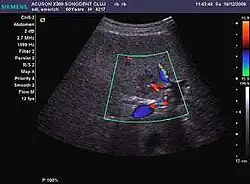

HCC appearance on 2D ultrasound is that of a solid tumor, with imprecise delineation, with heterogeneous structure, uni- or multilocular (encephaloid form). An "infiltrative" type is also described which is difficult to discriminate from liver nodular reconstruction in cirrhosis. Typically HCC invades liver vessels, primarily the portal veins but also the hepatic veins . Doppler examination detects a high speed arterial flow and low impedance index (correlated with described changes in tumor angiogenesis). The spatial distribution of the vessels is irregular, disordered. CEUS examination shows hyperenhancement of the lesion during the arterial phase. During the portal venous phase there is a specific "wash out" of ultrasound contrast agent (UCA) and the tumor appears hypoechoic during the late phase. Poorly differentiated tumors may have a stronger wash out leading to an isoechoic appearance to the liver parenchyma during portal venous phase. This appearance was found in approx. 30% of cases. The described changes have diagnostic value in liver nodules larger than 2 cm.